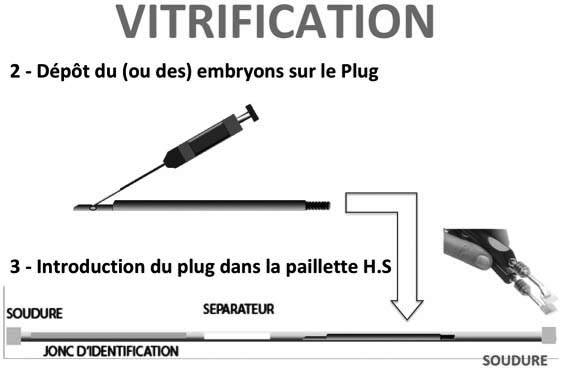

Ils sont ensuite disposés sur un une spatule spéciale qui sera introduite dans une paillette identifiée et fermée par soudure pour eviter toute contamination.

L’ensemble est ensuite plongé dans l’azote liquide à – 196 °C.et la vitrification se fait pratiquement instantanément.